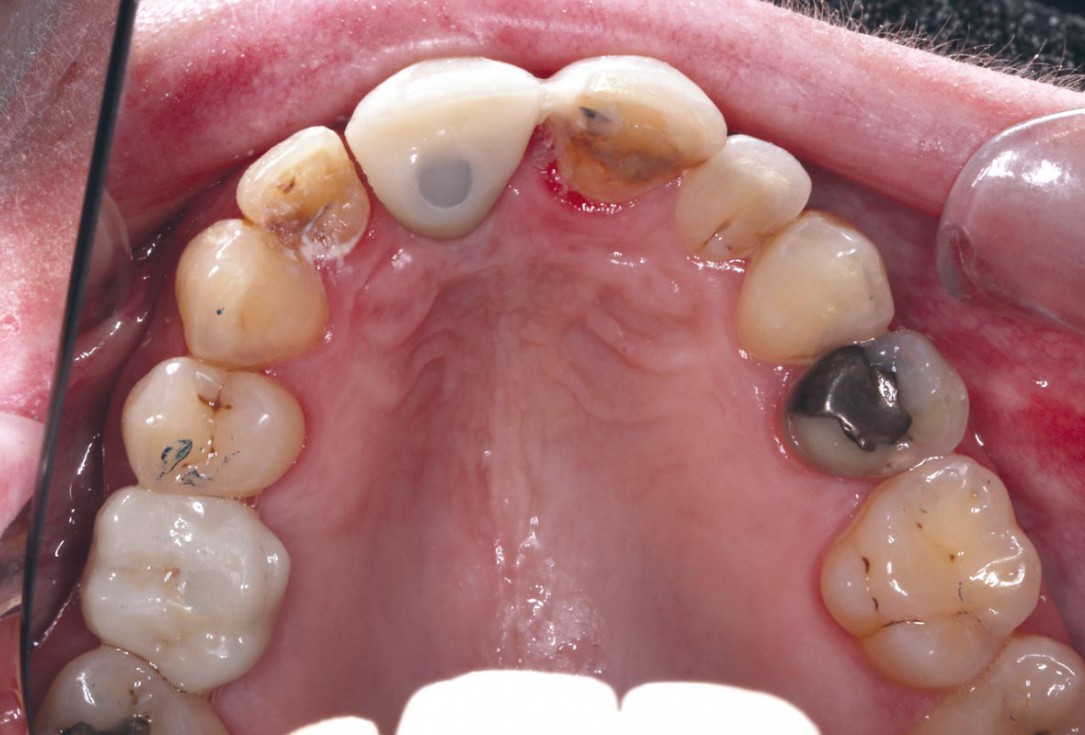

1/35 - Initial situation – Treatment plan: Replace the adhesive upper left central incisor bridge with a dental implantBlock grafting in the aesthetic zone with maxgraft®, Jason® membrane and cerabone® - Dres. H. Maghaireh and V. Ivancheva

Initial situation – Treatment plan: Replace the adhesive upper left central incisor bridge with a dental implant